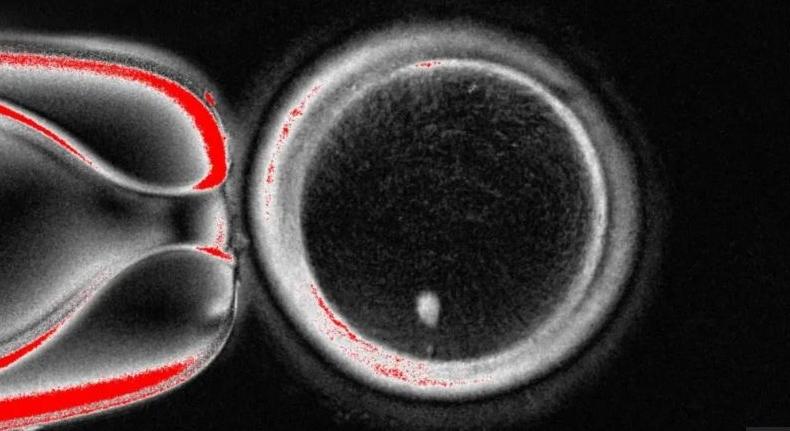

Az amerikai Oregon Health & Science University kutatói forradalmi áttörést értek el: első alkalommal sikerült emberi bőrsejtből létrehozniuk korai stádiumú embriókat. A módszer, amelyről a Nature Communications folyóirat számolt be, alapjaiban írhatja át a szülőségről eddig ismert szabályokat. A kutatás során a tudósok a bőrsejtekből vett sejtmagot helyeztek be egy donor petesejtbe, amelyből előzőleg [...] Read More... A tudósok először hoztak létre embriókat emberi bőr DNS-ből